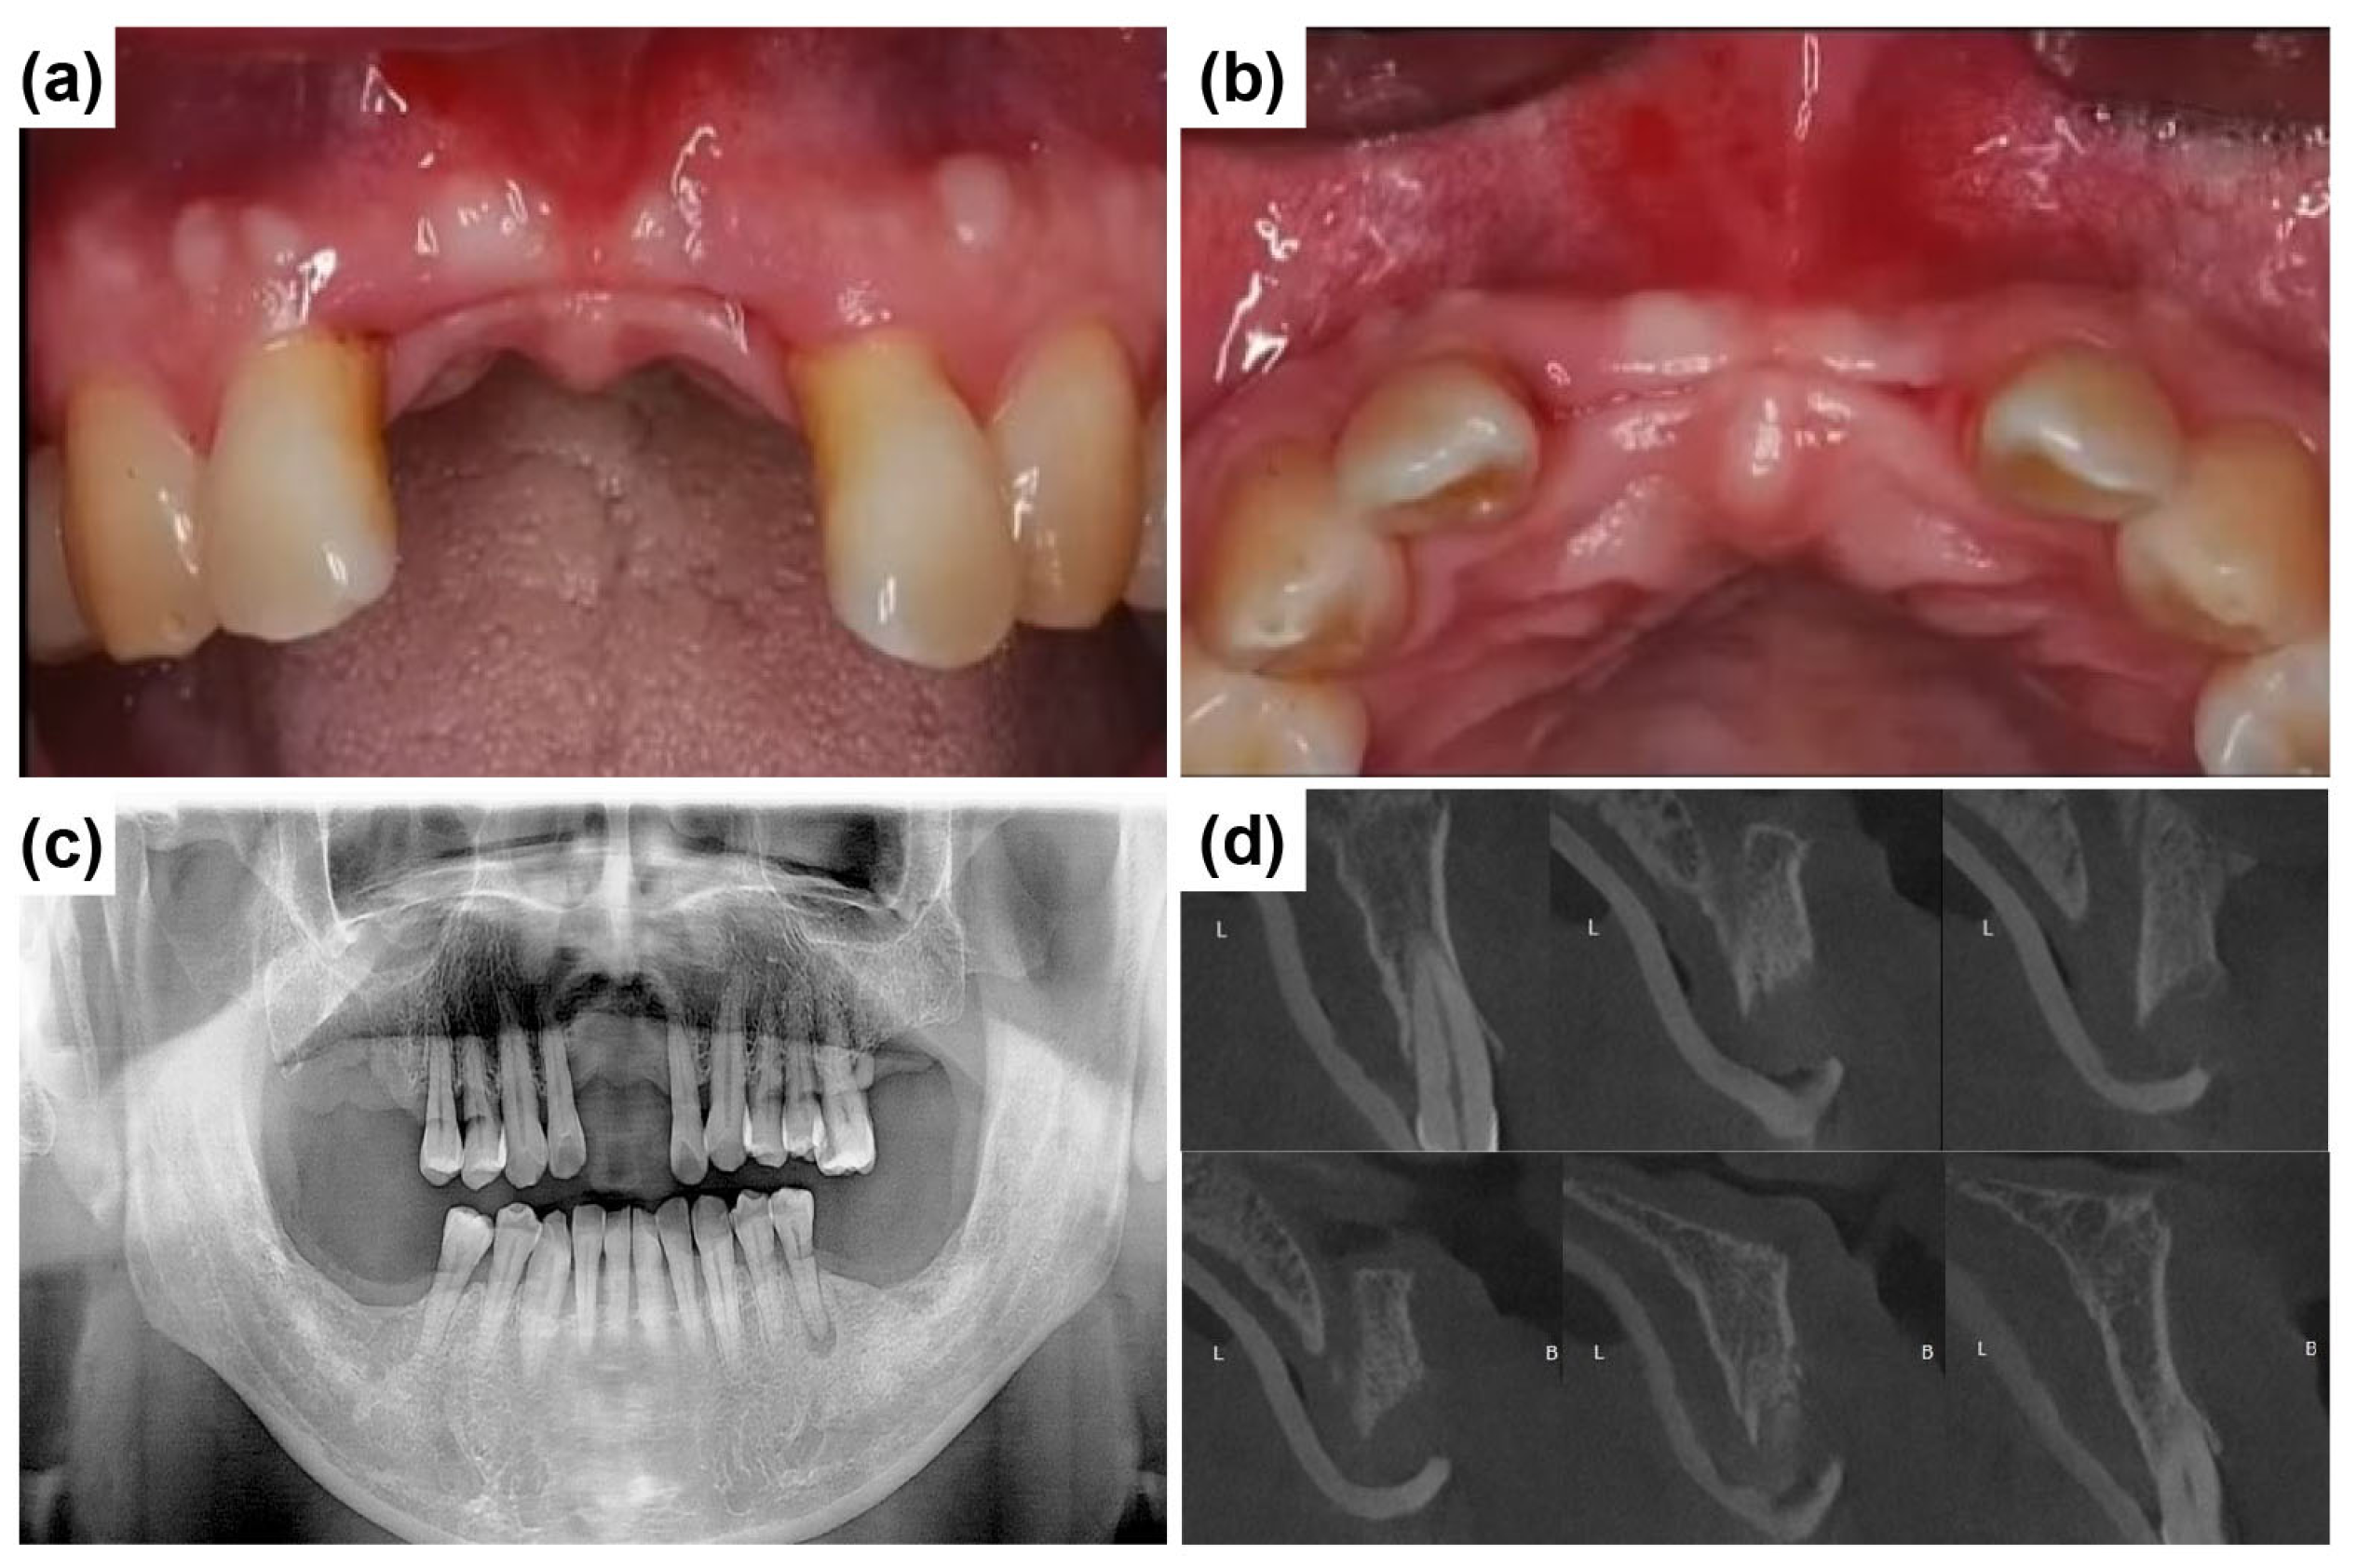

A 58-year-old male patient reported to Mir Dental Hospital at Daegu with missing maxillary central incisors (teeth #11 and #21). The patient was a heavy smoker but had no significant systemic conditions. He revealed that he had lost the teeth three months prior due to periodontal disease. Intraoral examination confirmed the absence of teeth #11 and #21. Figure 2a,b illustrate the clinical presentation at the initial visit, demonstrating severe alveolar ridge resorption and distinct U-shaped gingival recession. Radiographic evaluations, including cone-beam computed tomography (CBCT) and clinical examinations, were conducted to assess bone loss and optimize treatment planning. A panoramic radiograph revealed generalized poor periodontal health (Figure 2c), with notable horizontal alveolar bone loss and vertical bone defects in the edentulous region. Significant labial alveolar bone loss was observed, especially mesially around tooth #22 (Figure 2d).

Figure 2.

Preoperative clinical and radiographic evaluation. (a) Labial intraoral view of the anterior edentulous region (at the initial visit) shows the absence of maxillary central incisors (#11 and #21) and significant alveolar ridge resorption. (b) Occlusal intraoral view of the maxillary anterior ridge, severe horizontal ridge atrophy. (c) Initial panoramic radiograph shows the overall periodontal condition and alveolar bone status. (d) Preoperative intraoral periapical radiograph of the maxillary anterior region illustrates alveolar bone loss and root morphology before implant placement.